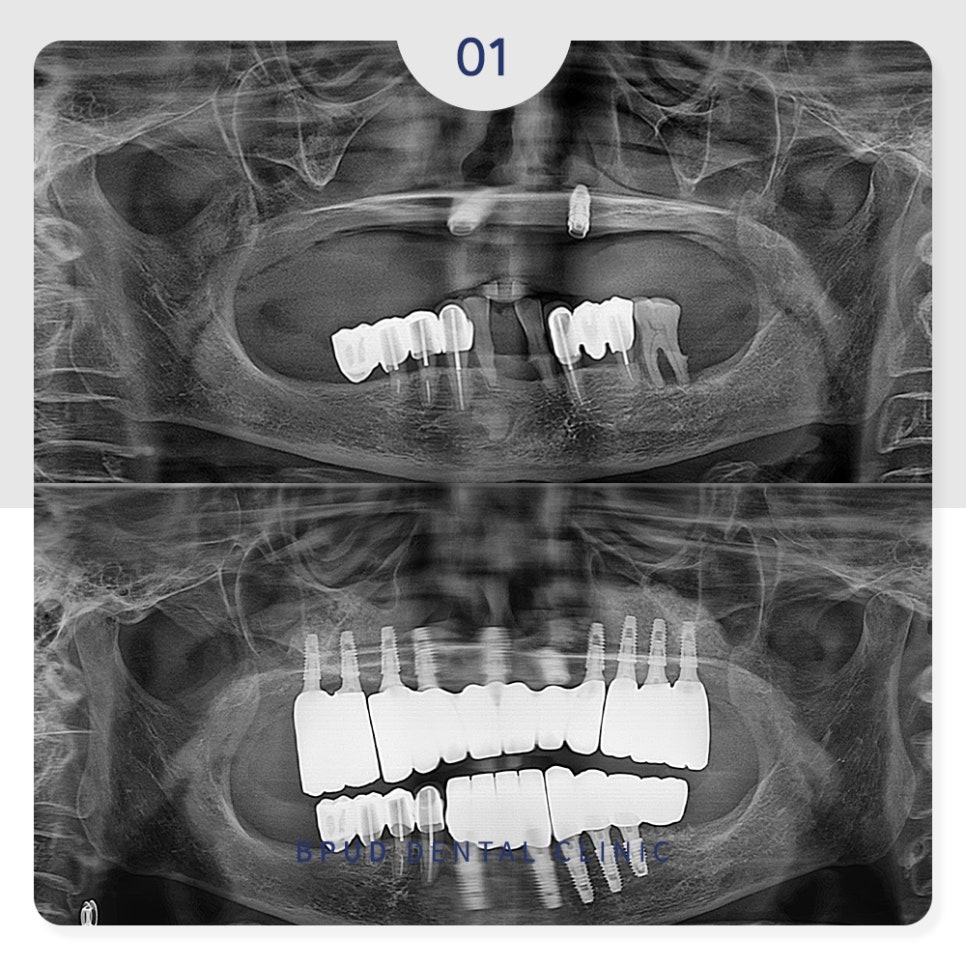

​22.04.09

아래쪽은 흔들림이 심했던 치아들을

발치하고 살릴 수 있는 치아들은 살린 뒤

어금니 부위를 연결한 캔틸레버 브릿지

형태로 마무리를 하였는데요.

아래쪽의 경우에는 발치 후 즉시 식립

진행 후 위쪽 임플란트를 제거하고

뼈이식을 동시에 시행하였습니다.

22.09.19

약 4~5개월 후 위쪽 임플란트도

식립을 진행하였습니다.